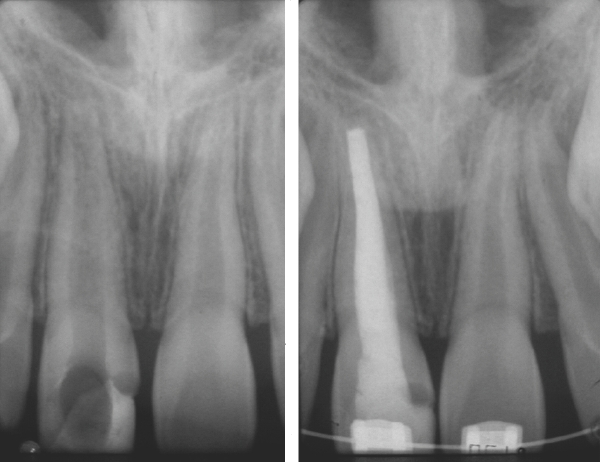

La apexificación es el tratamiento para crear un ambiente dentro del conducto radicular y los tejidos periapicales después de la necrosis pulpar, que permita la formación de una barrera calcificada a través del ápice abierto. La mejoría del conducto y del entorno apical permiten la reanudación, una vez más, del proceso interrumpido de desarrollo radicular y cierre apical. El resultado usual es el achatamiento del extremo de la raíz y poco o ningún aumento en la longitud.

La creación de un ambiente favorable para la formación de una barrera calcificada consiste en la limpieza minuciosa para eliminar bacterias y tejido necrótico del sistema de conductos, seguidas por la colocación de una pasta que permitirá la formación de una barrera calcificada en el ápice. El hidróxido de calcio se utiliza como material de obturación temporal. Es bactericida con un ph alcalino que pueda estimular la calcificación apical.